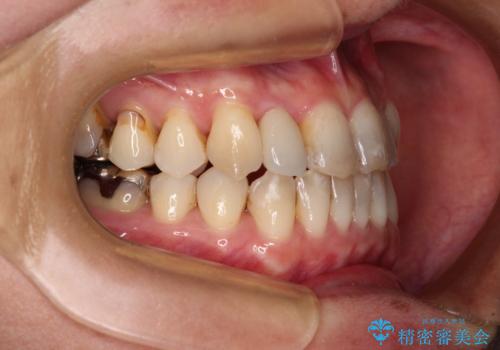

- 前歯の反対咬合を気にして来院された患者様です。

上顎骨の幅が下顎骨よりも小さいので、拡大装置により骨幅を広げて上下関係を改善すると同時にワイヤー矯正で反対咬合の改善を図り、その後インビザラインにて歯並びを整えることとしました。

上顎前歯の矮小歯は矯正治療の途中でオールセラミッククラウンを装着し、左右のバランスを整えることとしました。

急速拡大装置の使用により奥歯の咬み合わせが劇的に変わり、その変化を利用して反対咬合を改善することができました。

治療期間中は奥歯が咬み合わず、食事が取りにくいなどの不都合がありましたが、最終的にはきれいに整えることができました。